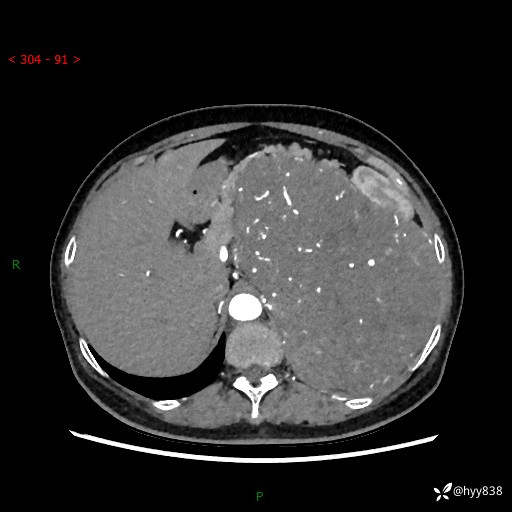

据说只有腹膜后,才能见到如此巨大的肿块---(有结果)

主诉:发现腹膜后占位1周

简要病史:患者1周前因头晕在当地第二人民医院检查发现左侧腹膜后区巨大富血供占位性病变,患者自诉腹部稍硬,无其他不适,无血尿,无腰痛等不适,患者为求进一步治疗来我院,门诊以“腹膜后占位性病变”收入我科。 起病以来,患者精神、饮食、睡眠可,大便正常,小便如上述,体力体重无明显改变。

临床诊断:腹膜后占位

腹部CT增强(动脉期+静脉期 ) ---平扫外院